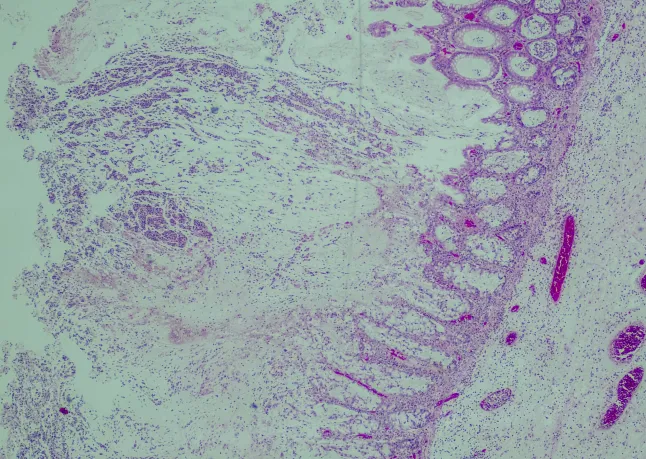

C. diff is a naturally occurring bacterium found in the human bowel and is often harmless. However, infections can develop when the gut’s bacterial balance is disrupted, often due to antibiotic use. Symptoms of a C. diff infection include severe diarrhoea, abdominal pain, and fever.